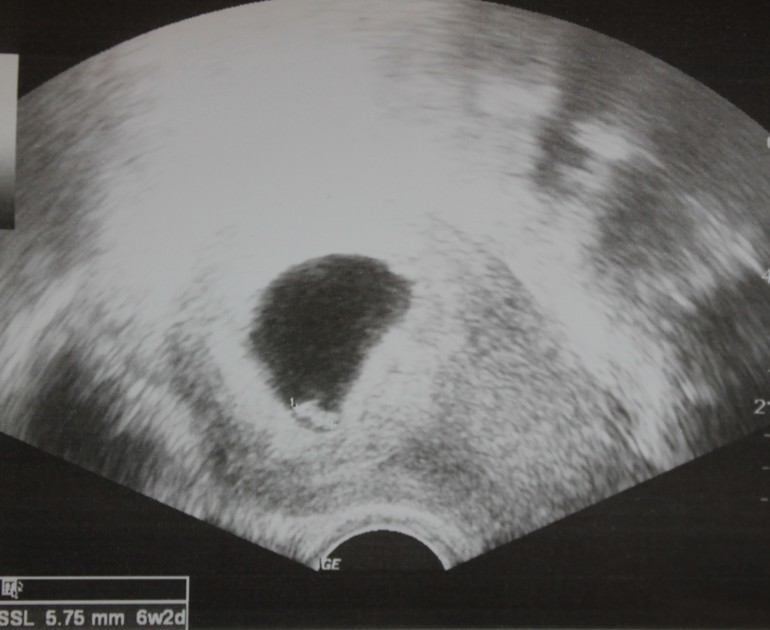

А вот и наша первая фотография! Кто бы мог подумать, маленькая кнопочка внизу черного пространства это и есть наш малыш)))

Далее, подходя к расчетам, доктор сказала, что по размерам мы отстаем примерно на 3-4 дня если считать от последних месячных. Но сказала, что пока оставим как есть, все таки впереди еще много наблюдений! Прийдя домой и начитавшись, немного волнительно... почти полных 7 недель, а кнопочка всего 5,75 мл. Девушки, а какие у вас были размеры на таком сроке?